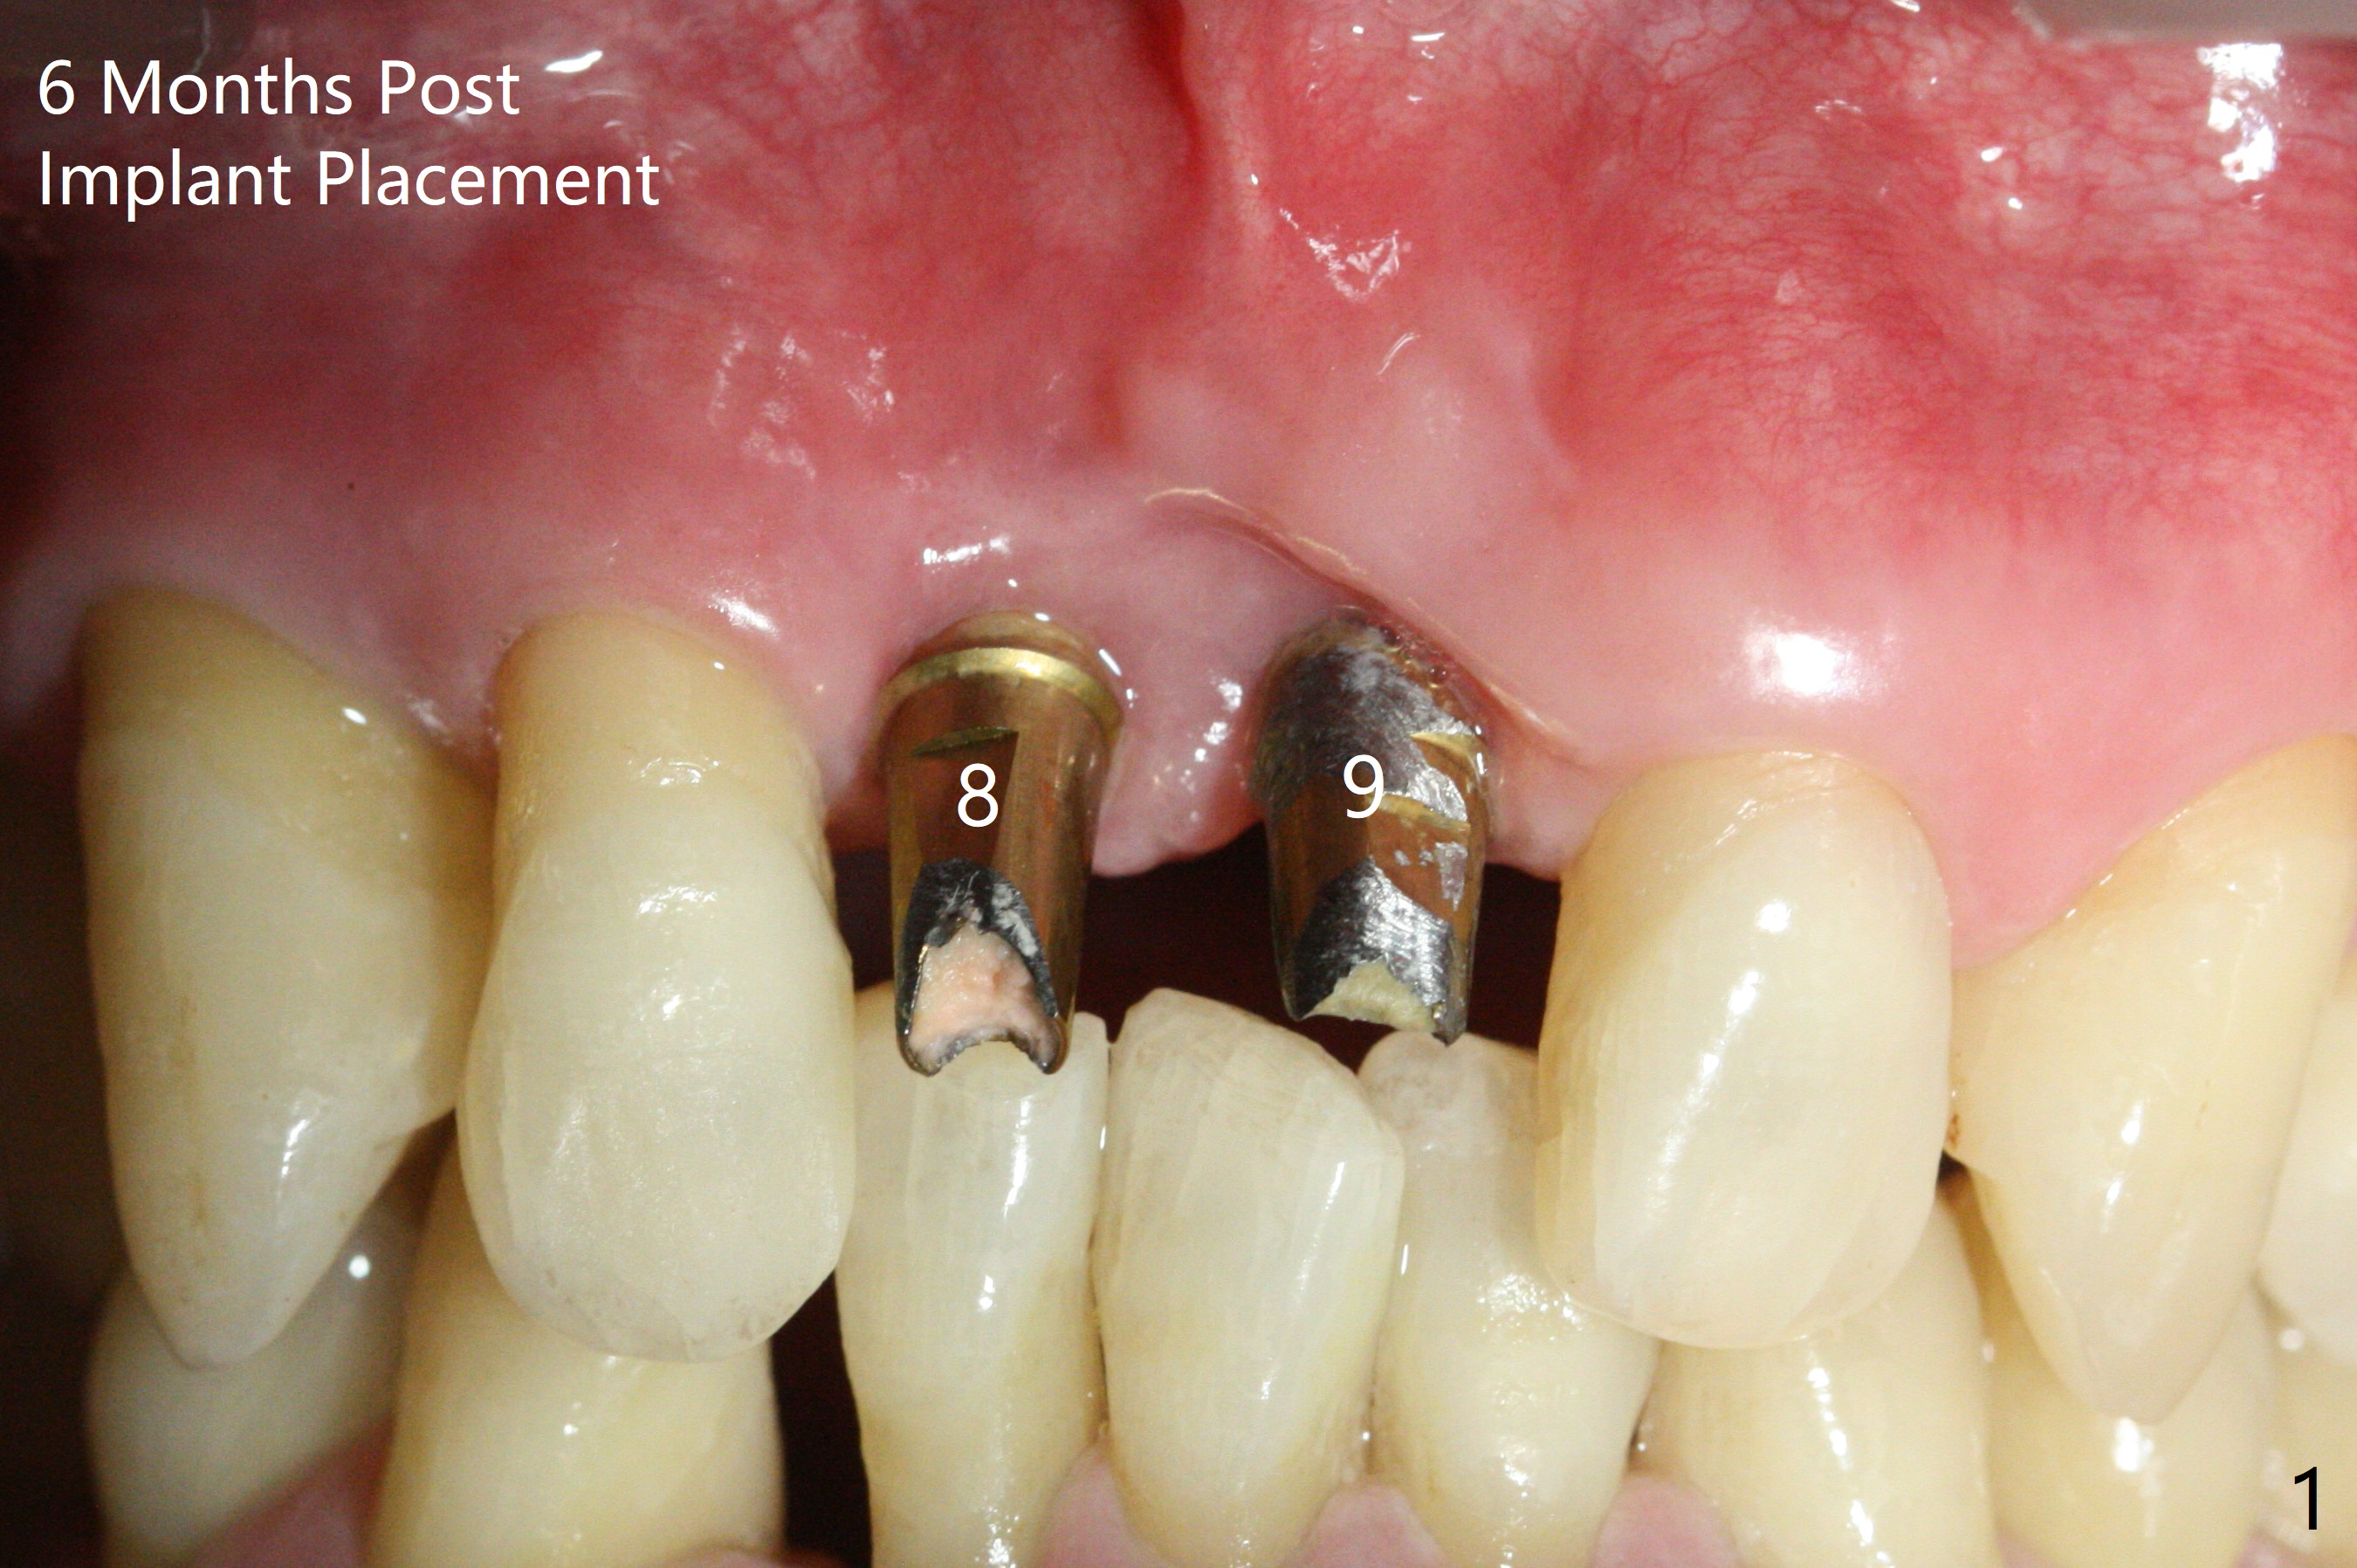

The gingiva remains recessive at #8 and 9 six months post immediate implant placement with bone graft (Fig.1). The buccal plate at #8 is particularly concave before (Fig.2 *) and after (Fig.3) abutment removal. The bony defect repair is assisted by placing a 4 mm tenting screw between the 2 implants (Fig.4) and placing allograft mixed with PRF (as putty) around the screw (Fig.5 (after replacement of the abutments)). The buccal contour improves because of the tenting screw and the bone graft placement (Fig.6 (as well as PRF and 6-month membranes)). The wound dehisces 12 days postop and immediately before leaving country for months (Fig.7). The sutures are removed, Osteogen plug is inserted (Fig.8) and periodontal dressing is applied (Fig.9). PA is taken to show the tenting screw (Fig.10 T). The latter is exposed 3 months postop (Fig.11,12). It appears that gingival graft is a must (Fig.13). Make a palatal stent, remove the temp with abutments and create a bleeding surface before harvesting a large piece of tissue. Connective tissue graft is done 5 months post bone graft (Fig.14). In fact there is no implant thread exposure. In fact the connective tissue graft does not survive. The abutments are re-prepared for pink porcelain (Fig.15). The bone loss is stable 1 year post cementation in spite of incomplete abutment seating (Fig.16). The soft tissue is nearly normal (Fig.17).